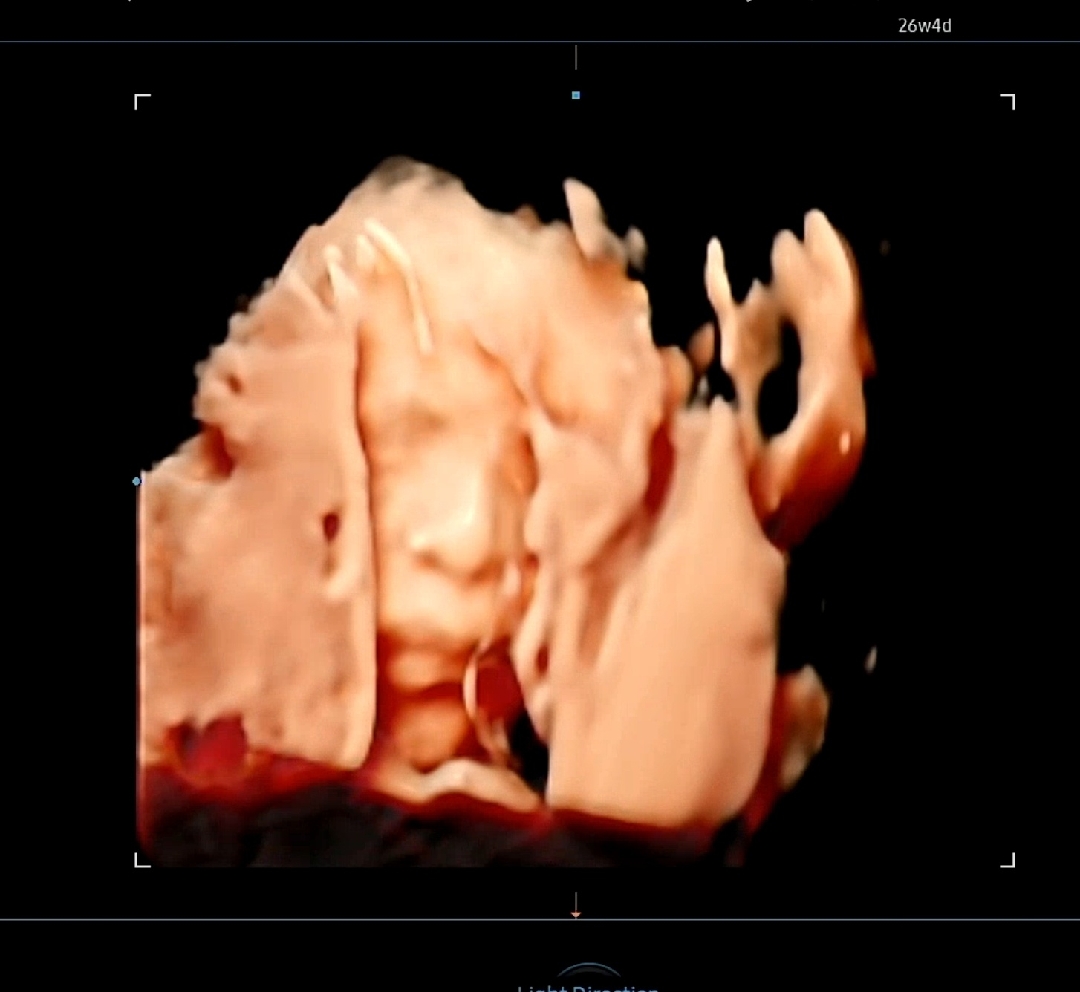

입체초음파...ㅜㅜ

자연유산, 시험관, 절박유산 진단, 쌍둥이 도태... 끝에 어렵게어렵게 지켜낸 아기라서 얼굴이 너무너무 보고싶었는데ㅜㅜ 초음파 선생님이 30분 넘게 봐주셨는데도 오늘은 이게 최선인가봐용ㅜㅜ (근데 저렇게 빼꼼 보이는 코랑 입술만으로도 제 눈에는 귀여워서 계속 보고있...네...요... 히히... ㅎㅎㅎ)

귀엽다고 해주셔서 정말 감사합니당♡ 30분을 계속 봐주신건 아니구 20분을 앞뒤좌우(?)로 봐주셔도 안되어서, 걷고 한 뒤에 다시 10분 정도 봐주셨는데, 계속 부끄러운지 태반쪽으로 얼굴을 돌리고 있더라구요😭😭😭